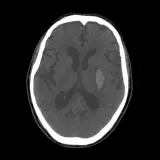

Over 2,100 interactive radiology cases, curated by radiologists for your level of training. Scroll, window, and view cases full screen โ€” just like on PACS. Click linked findings in each writeup to jump straight to them on the image. Cases include sample reports, a focused discussion section, original illustrations, and videos.

PACS์—์„œ ๊ธฐ๋Œ€ํ•  ์ˆ˜ ์žˆ๋Š” ๋ชจ๋“  ๋„๊ตฌ๋ฅผ ๊ฐ–์ถ˜ ์™„์ „ํ•œ ์ธํ„ฐ๋ž™ํ‹ฐ๋ธŒ ์ฆ๋ก€ — ์Šคํฌ๋กค, ์œˆ๋„์šฐ ์กฐ์ ˆ, ํ™•๋Œ€/์ถ•์†Œ, ํŒจ๋‹, ๊ณ„์ธก, ROI, ์ „์ฒด ํ™”๋ฉด ๋ชจ๋“œ๊นŒ์ง€ ์ง€์›ํ•ฉ๋‹ˆ๋‹ค.

์‹ค์ œ PACS ์›Œํฌ์Šคํ…Œ์ด์…˜์ฒ˜๋Ÿผ ์Šคํฌ๋กค, ํŒจ๋‹, ์œˆ๋„์šฐ ์กฐ์ ˆ, ํ™•๋Œ€/์ถ•์†Œ๊ฐ€ ๊ฐ€๋Šฅํ•ฉ๋‹ˆ๋‹ค